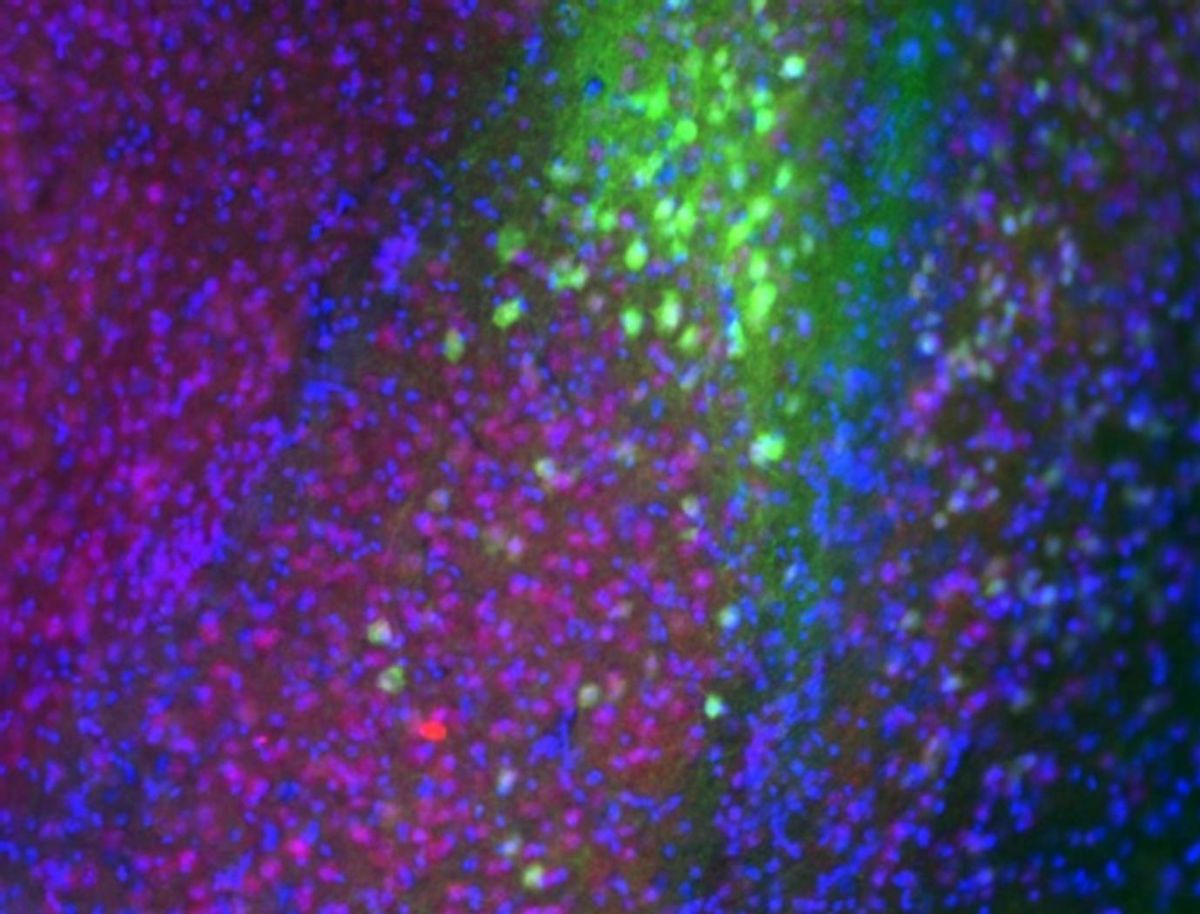

The rats also showed a disturbed rhythm for corticosterone, the body’s main stress hormone, as well as an increase in the number of receptors for corticosterone (the equivalent of cortisol in humans). In the amygdala, a region of the brain involved in learning fear, levels of a receptor for corticosterone were increased.

“We saw specific, long-lasting, probably permanent, changes in the amygdala,” Fanselow said.